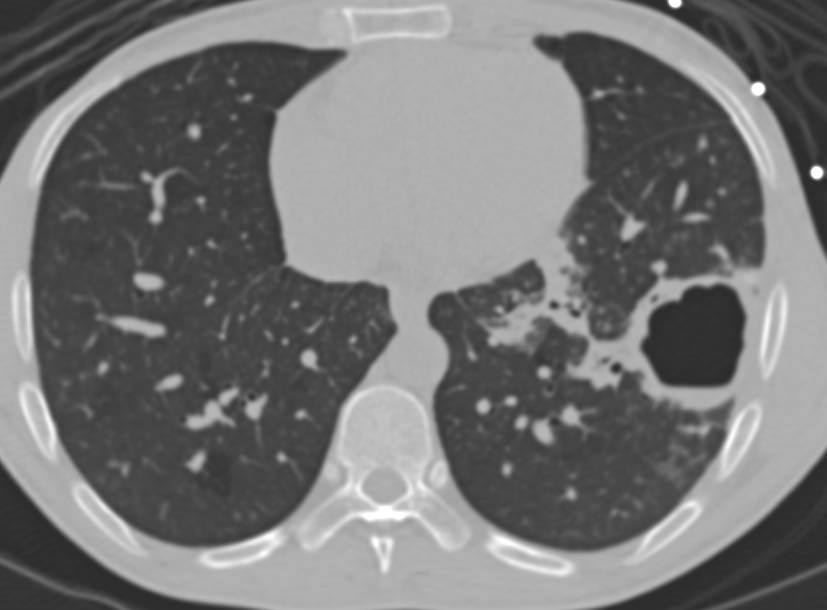

Визуализация и диагностика неинвазивного аспергиллеза с помощью КТ

Раздел: Необычные решения